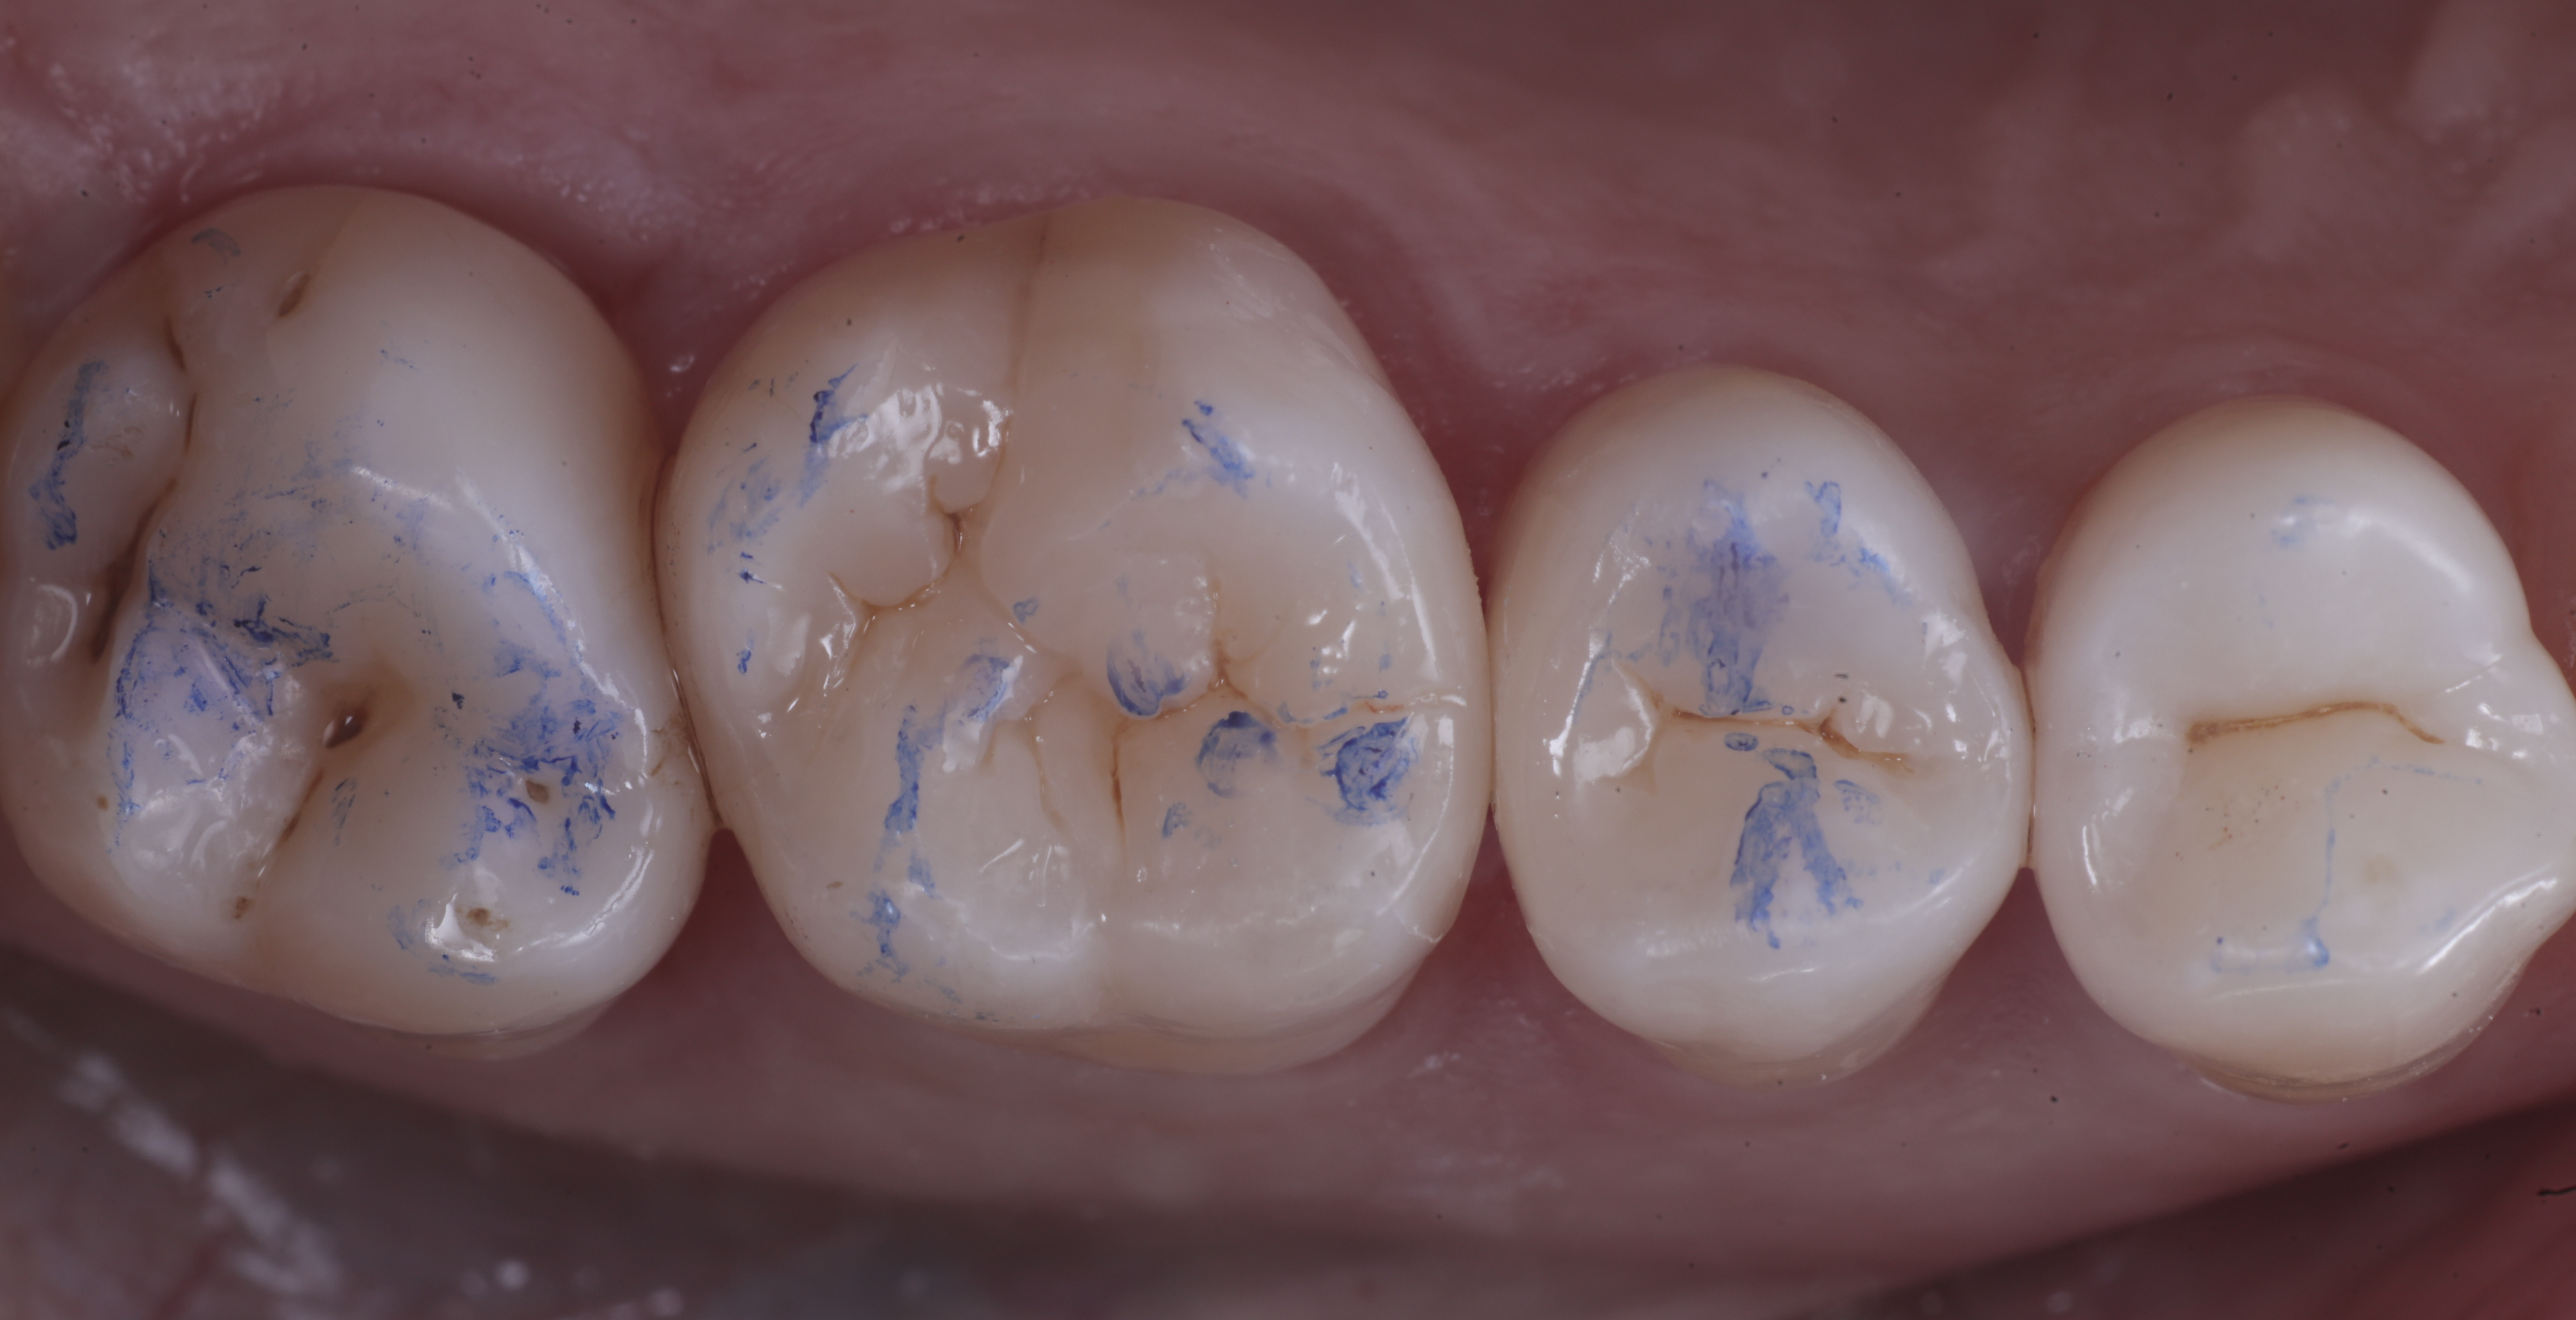

foto 11 Restauri ultimati sotto controllo occlusale

foto 8 Modellazione ed aspetto occlusale

foto 9 Modellazione ed aspetto vestibolare

foto 10 Modellazione ed aspetto palatino